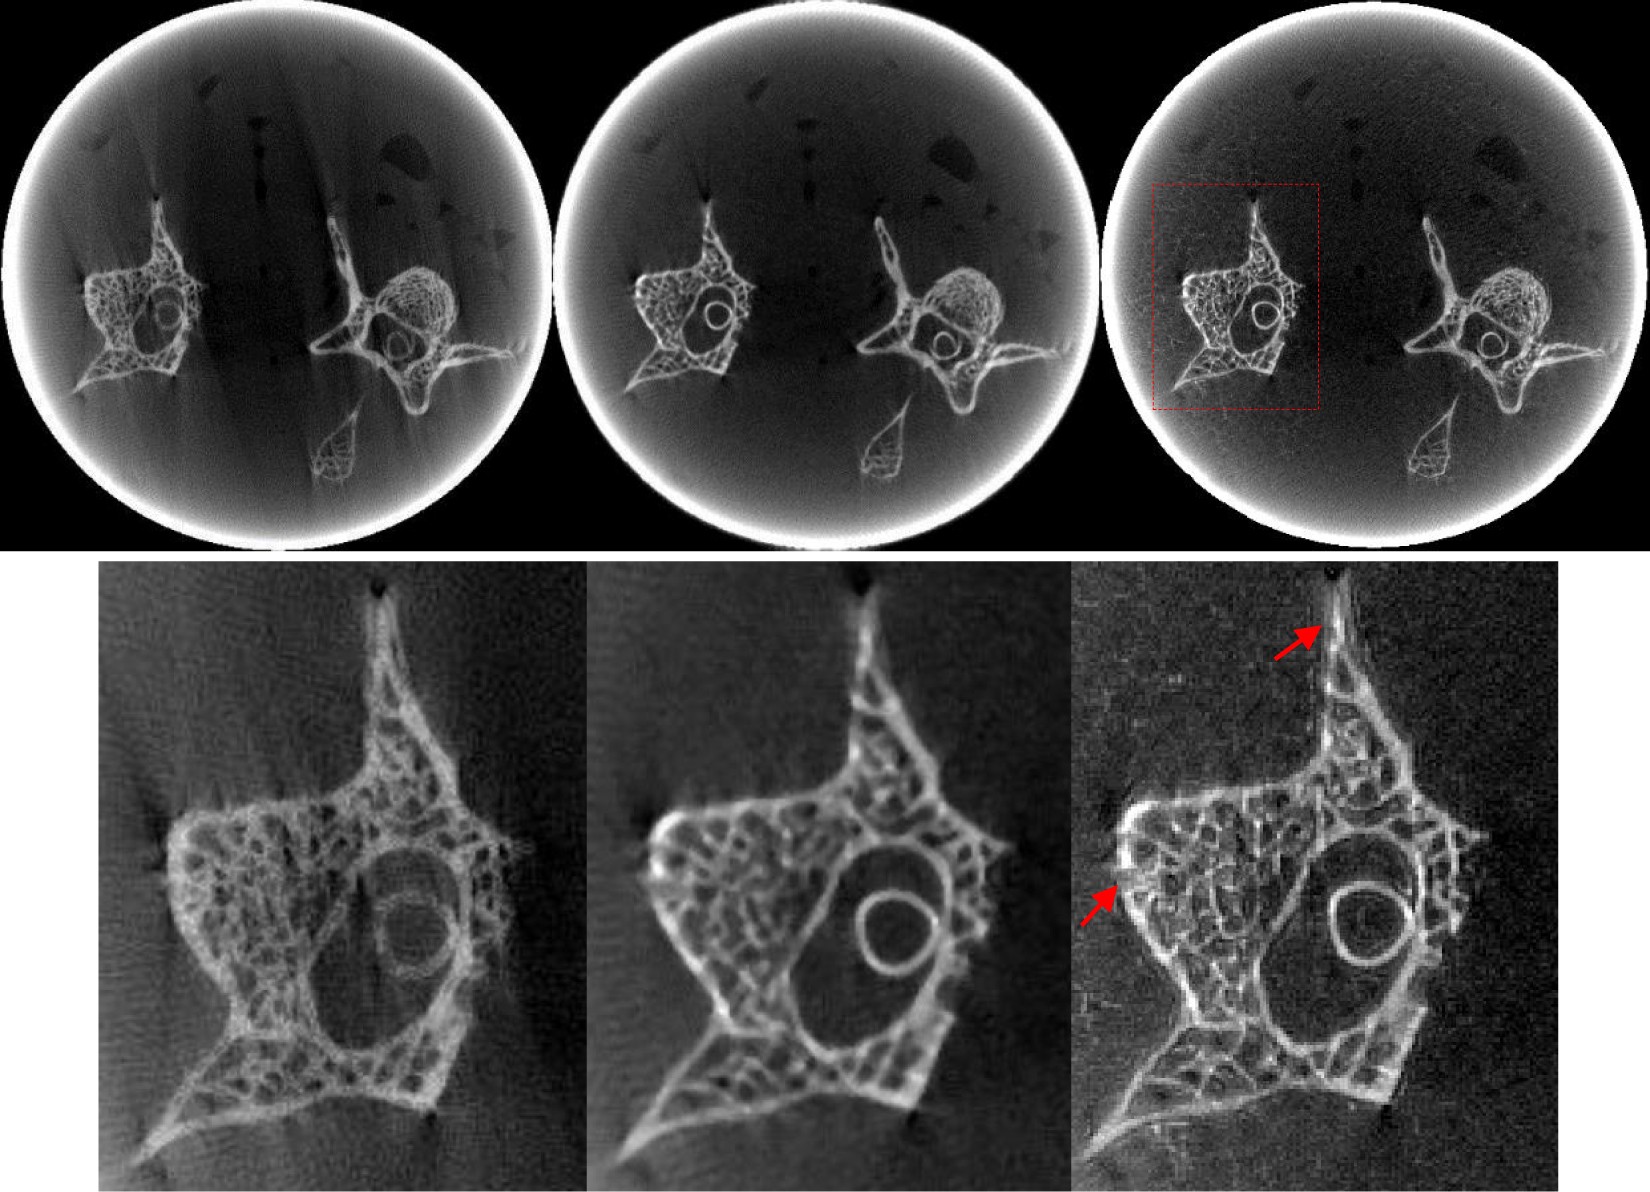

Figure 9

The mouse bone sample data collected over a 197.88° range reconstructions by different methods. From left to right, the images of the first row are the results obtained using FBP, PWLS-TV and PWLS-TV-FR method. The images of the second row are the partial enlarged view of the first row.